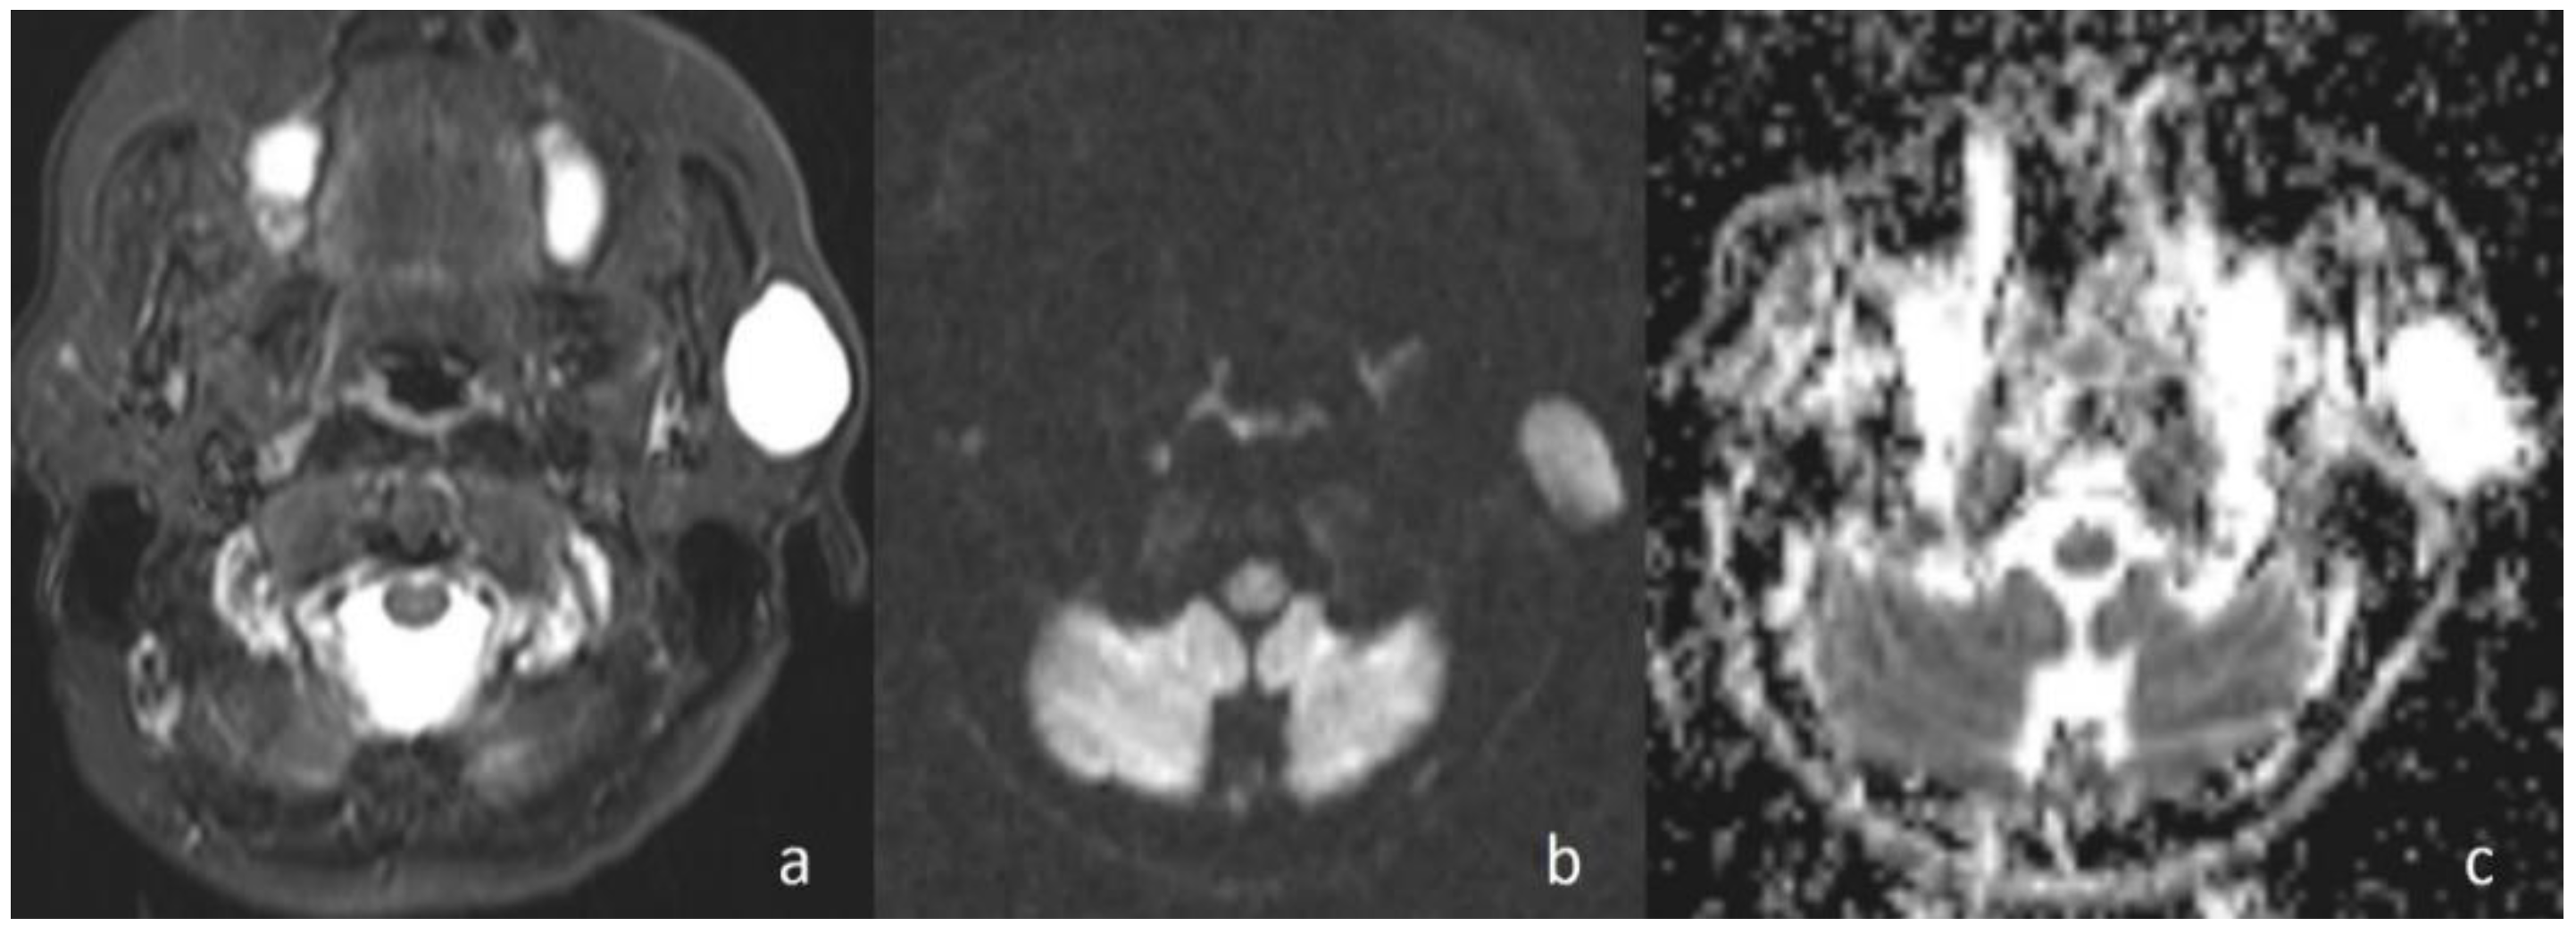

Figure 5. Non-Hodgkin lymphoma. (a) Axial T2WI shows metastatic cervical lymph node nearby SCM; (b) the lymph node, on the right side of the neck at level of lateral cervical region, shows high signal intensity on DWI; and (c) the mass is hypointense on the ADC map (ADC value of 0.62 × 10−3 mm2/s).

Sumi et al. [16] reported that the mean ADC value of lymphomas is lower than that of metastatic lymph nodes of carcinomas due to the difference in cellular density. Maeda et al. [17] also reported that carcinomas could contain small foci of necrosis on histopathological examination that was not identifiable on conventional MRI. This investigation has also been used to explain the higher ADC values of SCCs than those of lymphomas. In the current study, although there was no statistically significant difference, the mean ADC value of lymphomas (Figure 5) (0.80 × 10−3 mm2/s) was lower than that of the other malignant tumors (0.96 × 10−3 mm2/s). In the malignant group, larynx SCC metastasis with the value of 1.15 × 10−3 mm2/s showed the highest values.